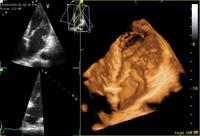

Plana, who is an ASE fellow and served as medical director of cardiac imaging at Houston’s MD Anderson Cancer Center, now heads a newly-formed cardio-oncology center at the Cleveland Clinic; every patient slated for a cancer therapy with toxicity potential receives an intensive left-ventricular mechanics protocol, which includes both 3-D echocardiography with contrast and strain imaging.